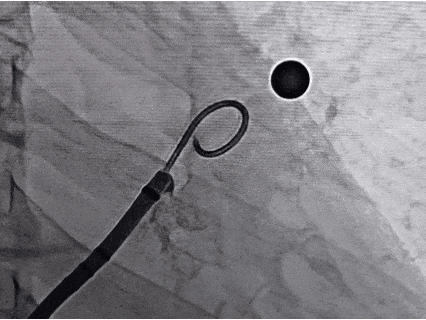

术中封堵器展开过程

导引鞘与推送鞘锁合后,退鞘缓慢展开左心耳封堵器